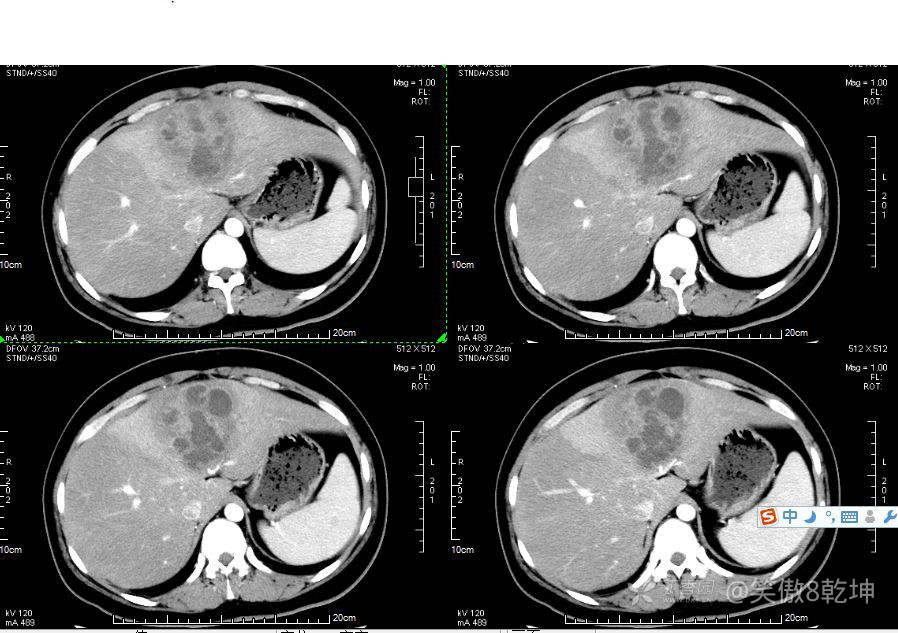

诊断似乎倾向于肝脓肿了,与患者或家属沟通后完善上腹部强化CT:

证实为肝脓肿,至此,诊断思路似乎清晰起来,患者血糖的升高使得微小血管容易出现循环障碍,同时白细胞的吞噬能力及抗感染能力下降,所有易出现感染性疾病。而肝脓肿通常不容易早期发现。患者的年龄同时让临床医生不容易想到此诊断。